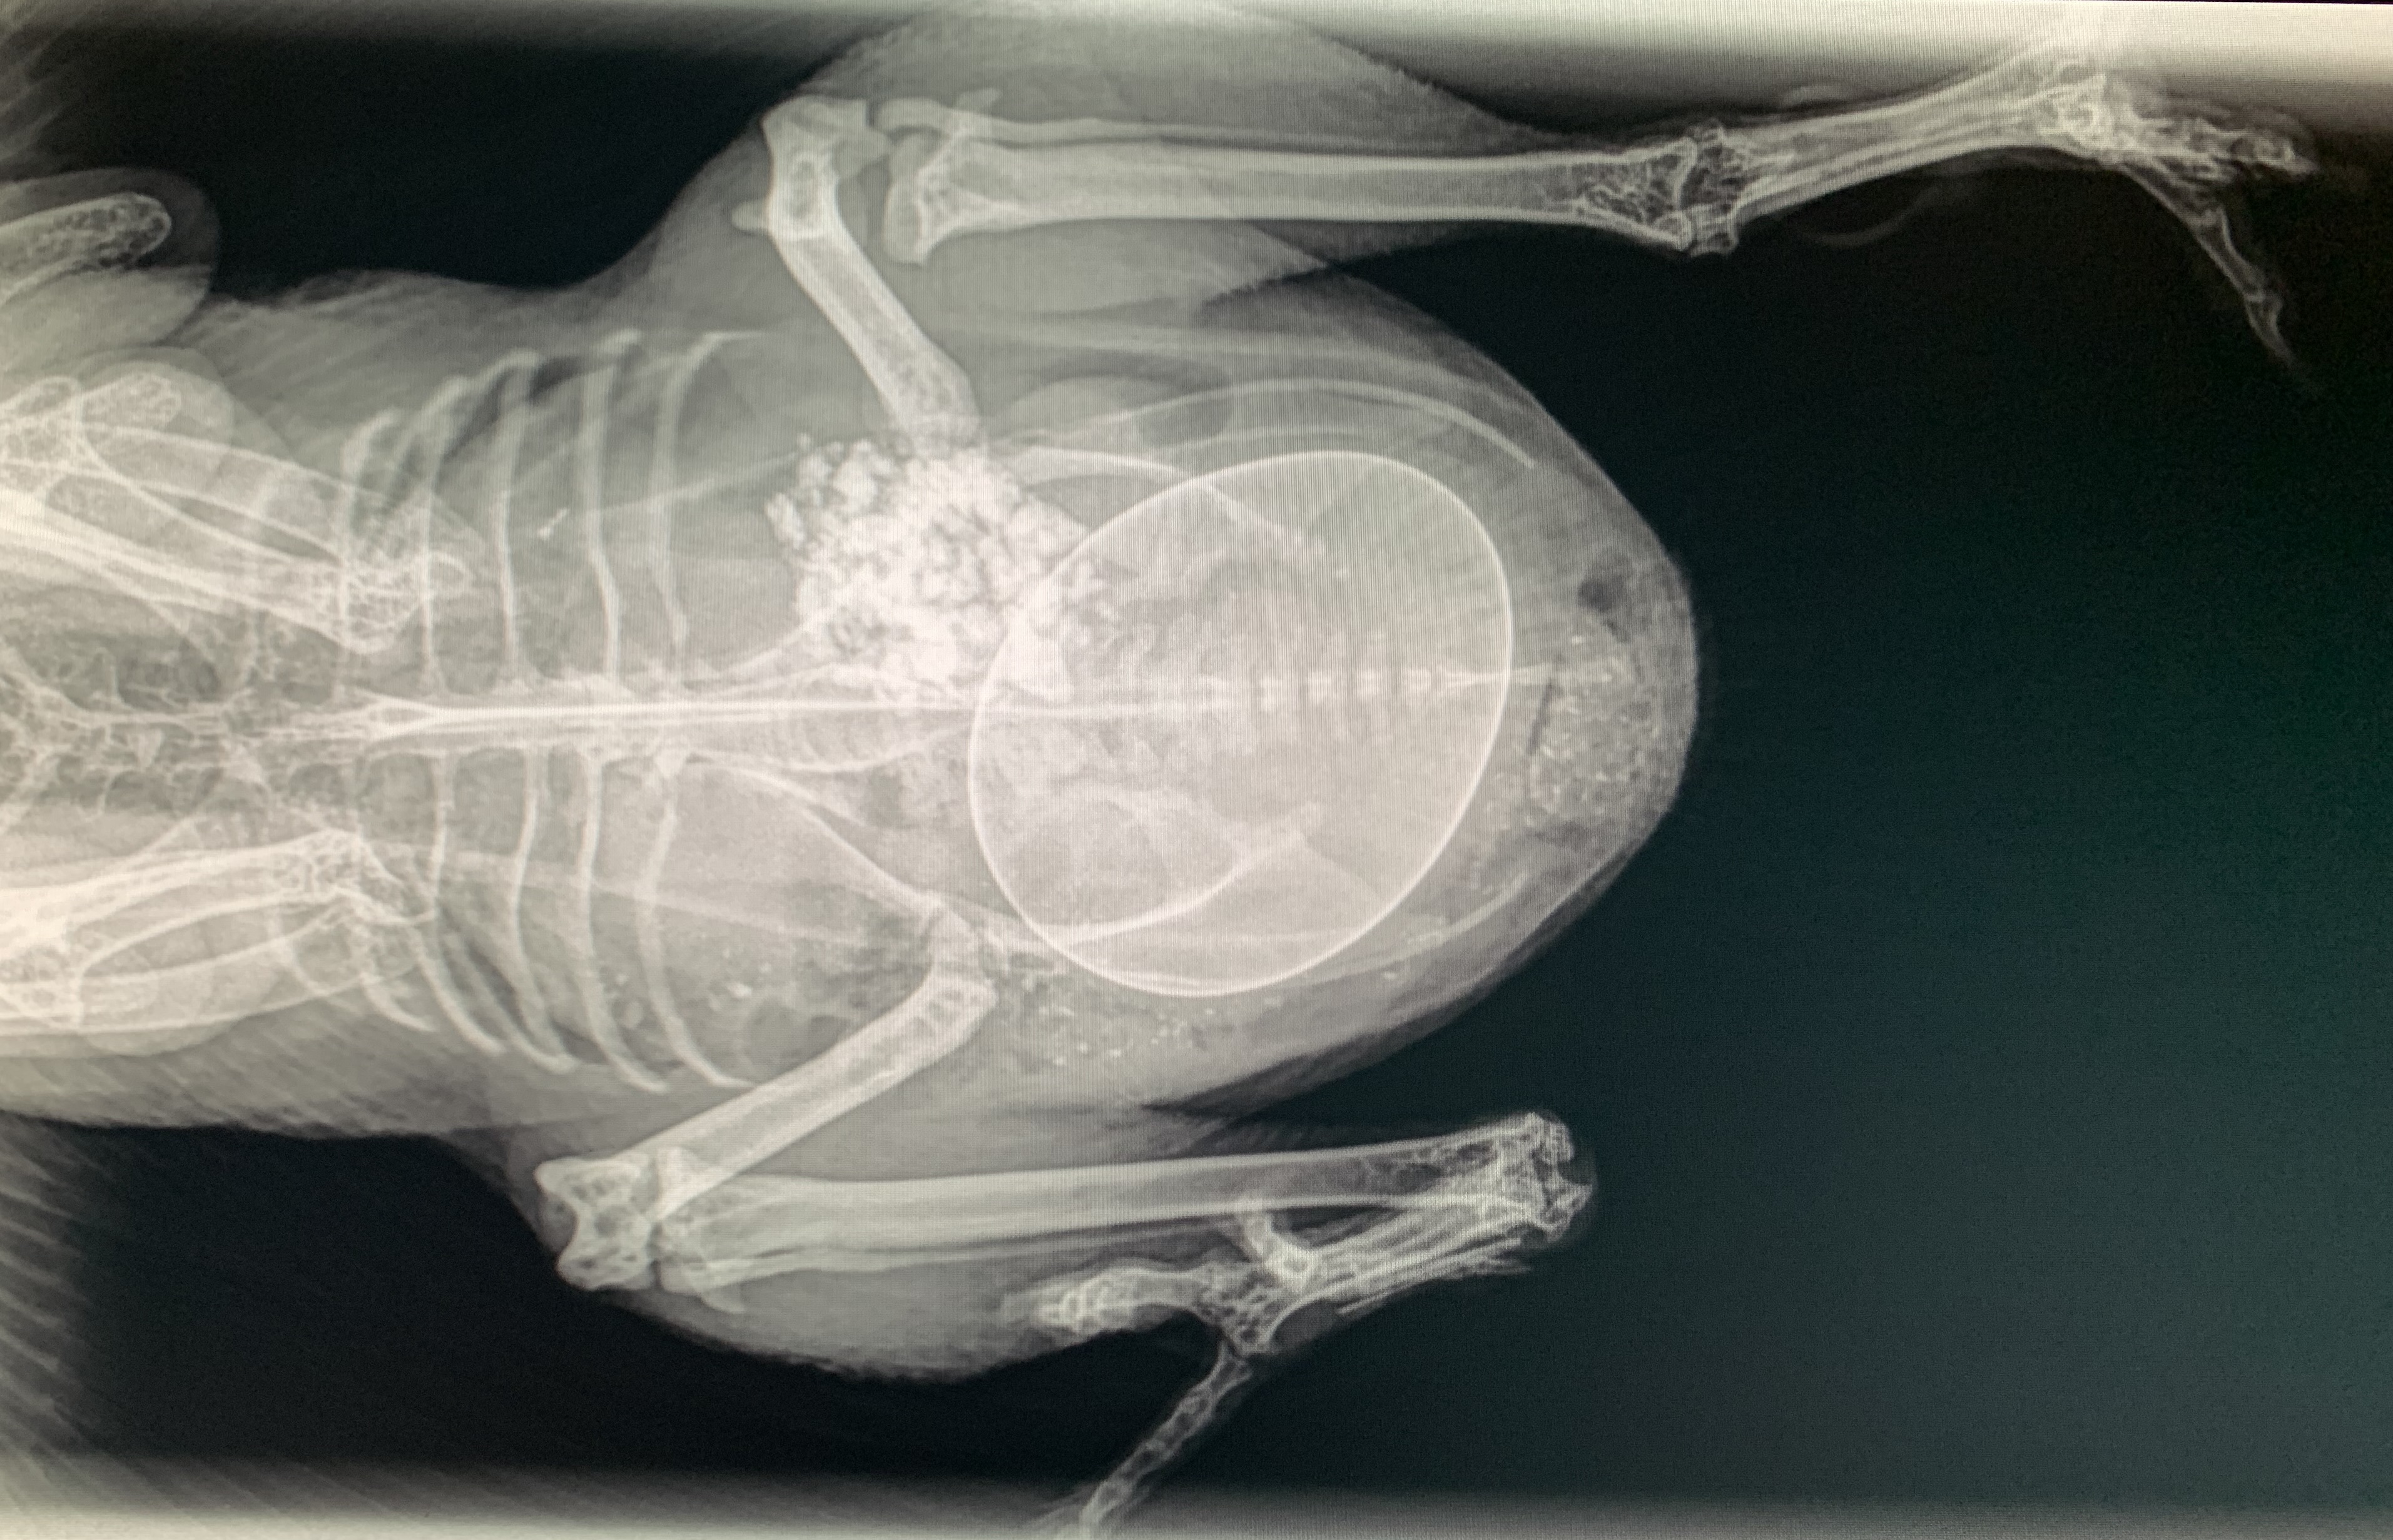

I lost Josie on May 30, 2024. She was my first Nankin hen, a real firecracker of a personality, and the matriarch to most of the first Nankins I bred in conservation of the breed. The week prior to her death, she had become egg bound. I tried giving her a half a chewable Tums, massaging her belly, giving her a dark place to lay and lubed up her vent, but nothing seemed to be working. I made an emergency appointment with one of my veterinarians who took radiographs to better see what we were dealing with. The egg was pretty large for no bigger bird than Josie was. She weighed a whopping 450grams.

Our veterinarian tried to manually get the egg into better position but was still unable to convince it to be laid. She gave her a dose of injectable Meloxicam and sent me off for an emergency trip to Denver to our avian board certified veterinarian. It’s about an hour and a half trip one way. We fully expected that Josie may need surgery to get the egg out since thus far it had not budged. Dr. F. was running a bit behind and dealing with several emergency cases, us included, so we had to wait for a bit in the exam room. While there, Josie pushed and pushed and finally laid that stupid egg! Wonderful!

Dr. F. looked her over and we decided to do a surgical hormone implant (which would prevent her from laying eggs) so we wouldn’t have such a disaster occur at a later date. I was always under the impression that once an egg bound bird laid the egg, you were home-free and in the clear to continue on with life as normal. So we did and Josie seemed to be feeling much better. But what if being egg bound wasn’t that simple at all? That, unfortunately, was the case for Josie.

About 5 days later, my son rushed into my bedroom and woke me up, “Something’s wrong with Josie! She is flopping around in the floor”. I rushed in to find just what he had described, but when I picked her up and examined her, I found that one leg was paralyzed and cool to the touch. I called our veterinarian and got her an appointment right away. At the visit they drew blood for me to take into work with me that evening. They also gave her pain medication and subcutaneous fluids. The veterinarian explained to me that sometimes in egg bound birds, the egg is so tightly wedged in their abdomen that it can put pressure on the surrounding organs and nerves. She did find it strange that it had taken a full five days for her to show any symptoms. She said she usually saw this complication in companion birds more often than in chickens and that it typically occurred within 24-48 hours past being egg bound.

The other thing that could have caused the paralysis is that her kidneys could have been damaged by the large size of the egg and the subsequent swelling of the kidneys could have compressed her sciatic nerve which in turn caused the paralysis. We wouldn’t know if that was the cause until the laboratory work was complete though. That night, I ran Josie’s chemistry panel and in 20 minutes I had my answer. Josie’s uric acid level was 259. A normal high uric acid was around 8. Josie was in kidney failure caused by a pressure necrosis from the large egg.